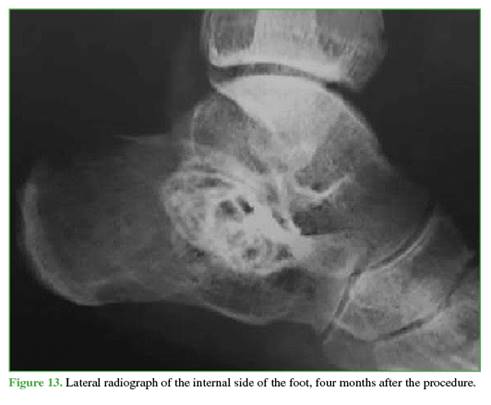

In successive clinical and radiological follow-ups, cyst ossification and pain resolution were confirmed (Figures 13-15). After more than two years of follow-up, the patient has not sought further medical consultation. Since ABC is known to have a recurrence risk, long-term monitoring should be maintained.